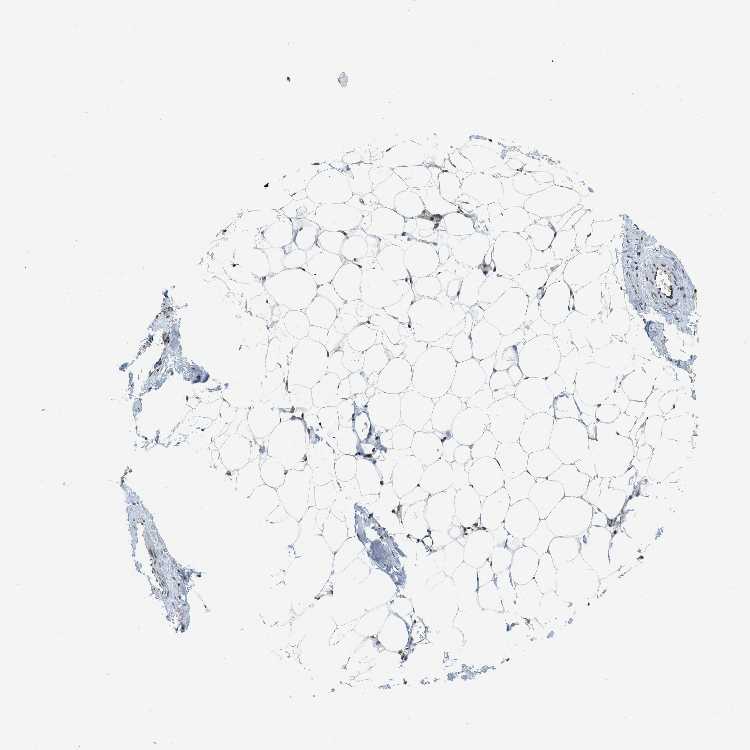

ADIPOSE TISSUE - Antibody stainingi

Antibody staining in the annotated cell types in the current human tissue is reported as not detected, low, medium, or high, based on conventional immunohistochemistry profiling in selected tissues. This score is based on the combination of the staining intensity and fraction of stained cells.

Each image is clickable and will lead to virtual microscopy that enables deeper exploration of all samples and also displays staining intensity scores, fraction scores and subcellular localization as well as patient and tissue information for each sample.

Antibody CAB017544

Adipocytes High